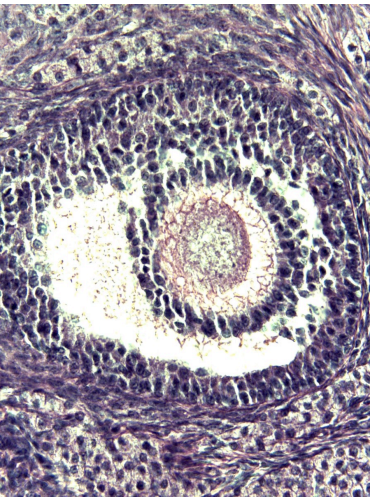

red

granulosa cells

orange

primary or secondary oocyte

yellow

oocyte nucleus

light green

zona pellucida

dark green

cumulus oophorus

light blue

antrum

dark blue

thecal cells

what is this

tertiary follicle

red

granulosa cells

orange

primary oocyte

what is this

primary follicle

red

granulosa cells

orange

thecal cells

yellow

zona pellucida

What is this

secondary follicle

red

granulosa cells

orange

thecal cells

yellow

primary or secondary oocyte

light green

cumulus oophorus

dark green

antrum

what is this

tertiary follicle

what is this

secondary follicle

what is this

tertiary follicle